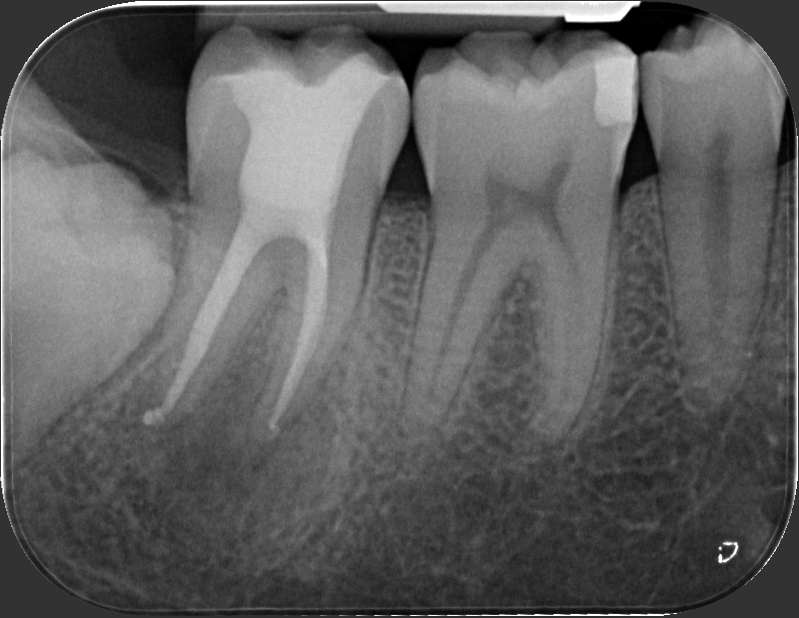

Caso clinico – trattamento ortogrado di 2° molare inferiore